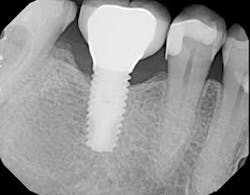

Figure 3:Note the extent of bone loss around the dental implant induced by the presence of excess cement.

Figure 11:Complete seating of the restoration confirmed radiographically.